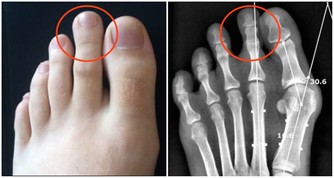

黃疸、肝臟腫大、肝區疼痛、脾大、腹水、下肢浮腫及肝功能異常,

還可能出現心臟擴大、肺水腫,甚至痙攣、昏迷等症狀。